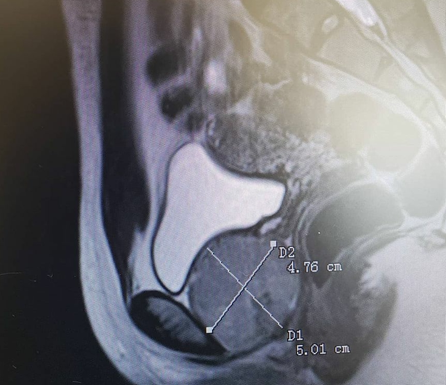

En cuanto a ayudas imagenológicas la cistouretroscopia y la cistouretrografía miccional (CUGM) pueden confirmar la presencia y ubicación de la estenosis uretral y, por lo tanto, llevar a un diagnóstico definitivo (Figura 3). Es importante destacar que la cistouretroscopia puede no ser factible en personas con estenosis del meato, estenosis uretrales distales y estenosis severa. En estos y muchos casos, la CUGM es esencial, ya que no solo puede diagnosticar definitivamente una estenosis uretral, sino que también proporciona información clave sobre la ubicación y la longitud de la estenosis uretral, lo que guía la planificación quirúrgica.

Tanto las imágenes tridimensionales como las imágenes por resonancia magnética (IRM) también pueden ser útiles, específicamente para identificar otras etiologías que pueden presentarse con síntomas similares como tumores primarios de la uretra. La fibrosis periuretral y otras afecciones pueden tener síntomas de presentación similares a la estenosis uretral y pueden identificarse en la resonancia magnética. La uretrografía por tomografía computarizada (TC) también puede ser útil en la evaluación tridimensional y tiene la ventaja adicional de simular la evaluación uretroscópica con una técnica llamada uretroscopia virtual por TC.16 (Tabla 1).